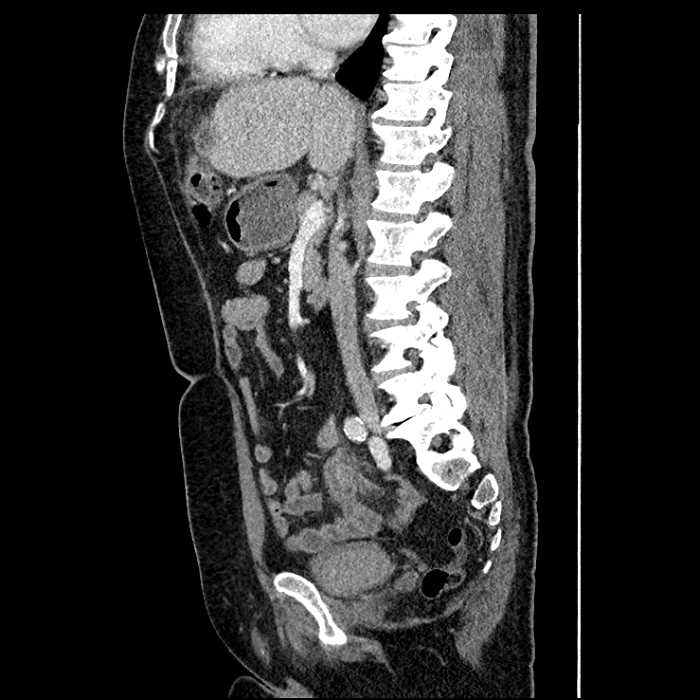

Acute sigmoid diverticulitis complicated by a small contained perforation and a large abscess in the right hepatic lobe. Additional small subcapsular abscesses along the anterior margin of the left hepatic lobe.

Additionally, loss of the normal fat plane between the peridiverticular collection and adjacent thickened loops of small bowel raises the potential for an enterocolonic fistula.

• The classic CT imaging appearance is a double target sign with internal low density surrounded by an internal enhancing rim (capsule) and a low density external rim (edema)

Hepatic abscess showing the double target sign with low density internally surrounded by a thin inner enhancing rim (red arrow) and ill-defined outer low density rim (yellow arrow). Blue arrow indicates an internal septation. Red arrows: additional smaller subcapsular abscesses. Red arrow: focal contained perforation associated with diverticulitis.